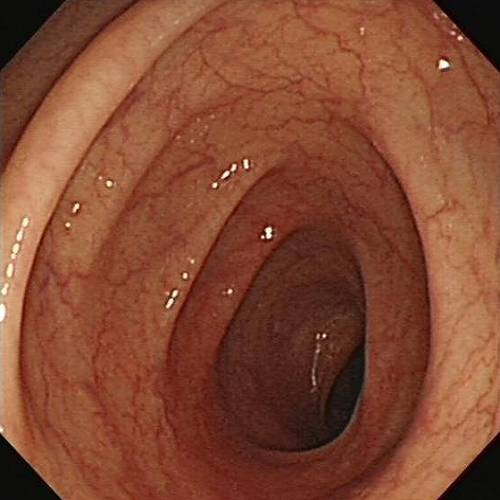

无图无真相,来看着这个图!

正常人的结肠VS 黑变病结肠▲

辣不辣眼睛?但是,结肠黑变病还不是最可怕的,最可怕的是滥用泻剂对于肠功能和肠动力的损害,这些是不可逆的!